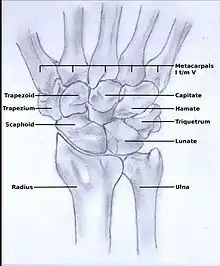

In order to understand the cause of post-traumatic wrist osteoarthritis it is important to know and understand the anatomy of the wrist. The hand is subdivided into three parts:

The wrist consists of eight small carpal bones. Each of these carpal bones has a different size and shape. They contribute towards the stability of the wrist and are ranked in two rows, each consisting of four bones.

In the treatment of stage II wrist osteoarthritis, there are two treatment options that have proved to be most successful. The first treatment option is proximal row carpectomy. During this surgical intervention the proximal row of the carpal bones is removed (scaphoid, lunate, triquetrum, pisiform).[15] It is important that the radioscaphocapitate ligament is left intact, because if the ligament is not preserved the capitate bone will translate to the ulnar side of the wrist and move away from the distal radius.[1][16] The new formed joint between the capitate and the lunate fossa of the distal radius is not as congruent as the former scaphoid-lunate-radius joint,[17][18] however the results of proximal row carpectomy are generally excellent.[18][19][20] In patients older than 40 years proximal row carpectomy is preferred because these patients have a small chance of developing osteoarthritis in the new formed capitate-radial joint during their remaining life.[7][21]

Patients younger than 40 years have a big chance to develop osteoarthritis in the radiocapitate joint. These patients have longer to live, therefore the incongruence of the joint will exist for a longer time. Thus, in this patient population four-corner arthrodesis is the treatment of first choice.[7] The capitate, lunate, hamate and triquetrum are bounded together in this procedure and the scaphoid is excised.[1][15] Before the arthrodesis is executed, the lunate must be reduced out of DISI position.[15] Because the radiolunate joint is typically preserved in stage II SLAC and SNAC wrists, this joint can be the only remaining joint of the proximal wrist. Both procedures are often combined with wrist denervation, as described in the text of treatment stage I.